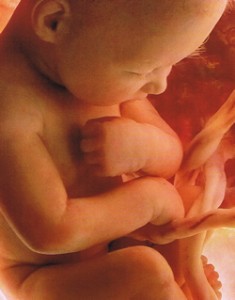

На 39-й неделе вес ребенка достигает 3 100-3 500 г, а его рост – 50-52 см. Показатели роста и веса весьма относительны и могут существенно отличаться. Малыш стремительно готовится к самому важному испытанию в своей жизни – рождению, которое требует выносливости и значительных усилий. В данный период беременности увеличиваются размеры и вес надпочечников ребенка, то есть желез эндокринной системы, которые отвечают за реакцию человеческого тела на стрессовые факторы. Именно вырабатываемые надпочечниками гормоны адреналин и норадреналин помогают ребенку максимально быстро приспособиться к новым температурным условиям, тактильным, звуковым и световым импульсам.

На 37-й неделе беременности рост малыша составляет приблизительно 48 см, а его вес – 2 600 г. Внешне плод почти не отличается от новорожденного, у него развиты все черты лица, ярко выражены хрящевые ткани. Накопление подкожного жира на таком сроке беременности делает очертания тела более мягкими и округлыми. Кожа ребенка постепенно разглаживается, она уже не такая розовая, как на предыдущих неделях внутриутробного развития, покровы постепенно светлеют. Тело малыша еще обильно покрыто смазкой, но количество пушка заметно уменьшается, пушковые волосы остаются только на плечах и спине, у некоторых малышей исчезают почти полностью.

На этой неделе продолжается накопление жировой клетчатки. Оно достигает максимального показателя – 15 % от общей массы тела ребенка. Сложно переоценить значение жировой ткани для новорожденных, именно она защищает ребенка от перегрева или переохлаждения, поскольку система терморегуляции малыша после родов еще недостаточно сформирована и продолжает развиваться в первые месяцы жизни маленького человека.

На данном сроке увеличивается не только объем подкожного жира, также интенсивно развиваются мышцы и скелет. Ребенок постоянно двигает ручками и ножками. Эти своеобразные тренировки способствуют увеличению мышечной массы. Также малыш совершает ритмичные дыхательные движения, которые укрепляют межреберные мышцы и диафрагму, готовят органы дыхания к родам.

38-я неделя беременности: развитие будущего малыша

На 38-й неделе происходит полное формирование плода, поэтому роды на данном сроке уже не опасны как для матери, так и для малыша. Масса плода составляет около 3 кг, однако данный показатель у разных малышей может существенно отличаться, вес зависит от индивидуальных особенностей мамы и ребенка, особенностей строения тела и других факторов. Длина тела новорожденного составляет приблизительно 50 см.

Все органы и системы на сроке 38 недель отличаются физиологической и морфологической зрелостью, они полностью готовы к работе. На этом сроке ребенок готовится к родам, совершает дыхательные движения и готовит межреберные мышцы к дыханию. Ткани легких омываются околоплодной жидкостью, которая способствует поддержанию нужного уровня сурфактанта, покрывающего легкие младенца изнутри. Все элементы дыхательной системы готовы к использованию. С первым вдохом после рождения альвеолы начинают передавать кислород из воздуха в кровь, происходит газообмен, дыхательная и кровеносная система начинают интенсивно работать.

39-я неделя беременности: что происходит с плодом?

На 39-й неделе вес ребенка достигает 3 100-3 500 г, а его рост – 50-52 см. Показатели роста и веса весьма относительны и могут существенно отличаться. Малыш стремительно готовится к самому важному испытанию в своей жизни – рождению, которое требует выносливости и значительных усилий. В данный период беременности увеличиваются размеры и вес надпочечников ребенка, то есть желез эндокринной системы, которые отвечают за реакцию человеческого тела на стрессовые факторы. Именно вырабатываемые надпочечниками гормоны адреналин и норадреналин помогают ребенку максимально быстро приспособиться к новым температурным условиям, тактильным, звуковым и световым импульсам.

Все органы чувств ребенка в 39 недель развиты. Уже через несколько мгновений после рождения малыш может сфокусировать взгляд, он реагирует на яркий свет и движущиеся предметы, многие ученые утверждают, что новорожденные различают цвета, видят лица родителей и врачей. Слух малыша на последних неделях внутриутробной жизни также полностью развит, после рождения он реагирует на громкие звуки и шум. Новорожденный малыш умеет определять основные оттенки вкуса, распознавать кислое, горькое, сладкое и соленое.

В матке ребенок находится в водной среде, которая сводит к минимуму контакты. Непосредственно после рождения малыш испытывает множество тактильных ощущений, в отличие от внутриутробной жизни, он чувствует прикосновения маминых рук и пеленок, полотенца, перевязочных и других материалов. Особенно нравятся малышам прикосновения кожи к коже, поэтому в современном роддоме новорожденных обязательно выкладывают на мамин живот еще до перерезания пуповины. Ребенок легче адаптируется к новой среде, чувствует себя защищенным. Выкладывание ребенка имеет не только психологический аспект, поскольку оно способствует заселению микроорганизмов с кожи матери на кожу и слизистые оболочки малыша, повышает его иммунитет.

40-я неделя беременности: как развивается малыш?

40 недель – доношенная беременность. Вес ребенка, который родился на таком сроке, составляет от 2 600 г до 4 400 г, а длина его тела – 48-53 см. Данные показатели весьма условны, поскольку на сроке 40 недель рождаются миниатюрные малыши весом 2 600 г и настоящие богатыри, масса тела которых приближается к отметке 5 000 г. Длина тела новорожденных также может варьироваться от 45 до 55 см.

Большинство женщин рожает именно в 40 недель. На этом сроке малыш полностью готов к рождению, он соответствует всем параметрам доношенного ребенка. Перед родами ребенок тесно прижимает ручки и ножки к телу, максимально сгибает головку и прижимается к выходу из матки. Такая поза позволяет сделать возможным прохождение родовых путей самой узкой частью черепа. В ходе родовой деятельности с каждой схваткой ребенок постепенно продвигается вниз, он не двигается по прямой, а совершает винтообразно-поступательные движения, как бы ввинчиваясь в родовые пути матери. В ходе продвижения новорожденного, полного опущения его головки шейка матки полностью раскрывается. Далее следуют потуги, то есть сокращения матки, которые продвигают ребенка по родовым путям. Постепенно показывается головка малыша, а следом за ней – его туловище. Роды – сложный механизм, который направлен не только на безопасное прохождение родовых путей ребенком, защиту его от случайных травм вследствие повышенного давления, но также на предотвращение разрывов мягких тканей женщины.